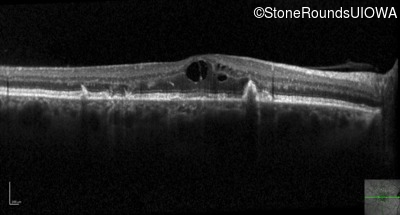

Optical Coherence Tomography - Left - 20/32 sc

Exemplar / OCT Stack

OCT Stack